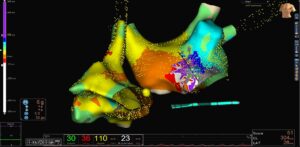

3D LAT Activation Mapping: Identifying the Circuit

LAT activation mapping demonstrated a macro re-entrant circuit in the left atrium.

The mapping confirmed a scar-related re-entry pattern

Propagation mapping showed wavefront circulation consistent with atypical LA flutter

In post-CABG patients, surgical scarring and atrial remodeling often create slow-conduction channels. These channels act as substrates for re-entry.

The propagation map clearly visualized wavefront movement around a scar region, confirming the arrhythmia was left atrial in origin rather than typical right atrial cavotricuspid isthmus flutter.

Ablation Strategy: Correlation with ILAM and Voltage Map

The ablation strategy involved correlating:

Isochronal Late Activation Mapping (ILAM)

Voltage mapping of the left atrium

The critical isthmus was identified along the anterior mitral region.

As shown on, the linear lesion connected anatomical landmarks to interrupt the re-entry circuit permanently.

Creating a complete conduction block across this line is essential to prevent recurrence.